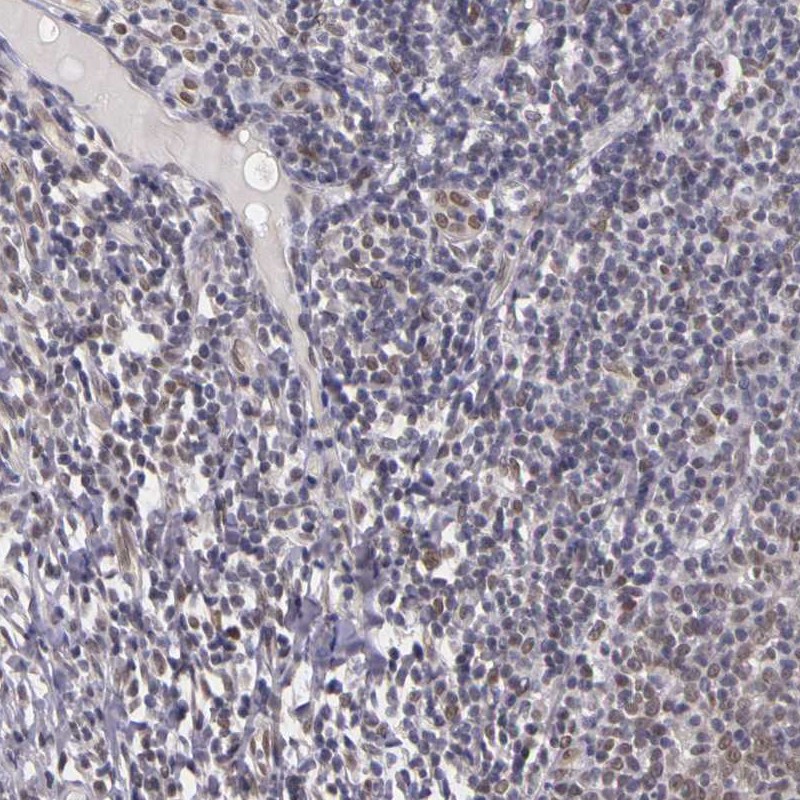

Immunohistochemistry analysis in human fallopian tube and tonsil tissues using Anti-WDR13 antibody. Corresponding WDR13 RNA-seq data are presented for the same tissues.